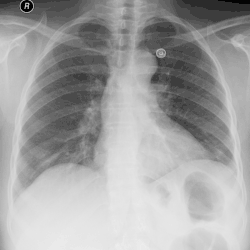

![]() Ewolucja ropniaka opłucnej na serii zdjęć RTG klatki piersiowej wykonanych w przeciągu 2 tygodni. | |

Badanie fizykalne wykazuje w obszarze przylegania płuca lub klatki piersiowej w miejscu płynu oraz osłabienie lub zniesienie szmeru oddechowego. Badanie radiologiczne uwidacznia zacienienie charakterystyczne dla płynu. Punkcja wykazuje ropny charakter wysięku. Stosuje się również do badania bakteriologiczne i cytologiczne.